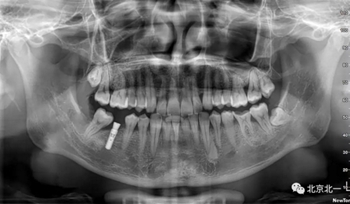

術(shù)后拍片。

正畸支抗直立47

第一次支抗釘脫落, 第二次支抗釘位于48位置, 頰側(cè)舌側(cè)舌側(cè)扣牽引。

直立后維持位置, 并取模戴牙。